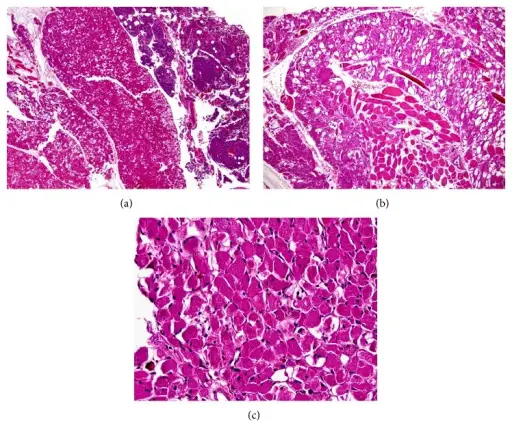

A lipoma is a benign tumor composed of adipose tissue that typically develops just beneath the skin.

Definitive diagnosis of lipoma is made by pathology showing a well circumscribed mass composed of benign adipocytes.